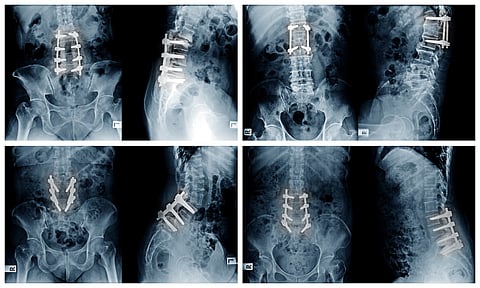

Key TakeawaysOrthopedic surgeons need to adapt low back procedures based on a person’s sexMen have narrower pelvises than women, making it harder to place rods and screws in a straight lineIf not anticipated, this can make surgeries longer and require surgeons to bend rods to fit the patient’s anatomy.FRIDAY, Oct. 17, 2025 (HealthDay News) — The placement of orthopedic screws and rods during spinal fusion surgery should vary depending on whether you’re a man or a woman, according to a new study.Sex-based anatomical differences in the pelvis make it essential that surgeons approach men and women differently when fusing and stabilizing the spine, researchers recently wrote in the journal Spine Deformity.Men have a narrower pelvis, which means that screws and rods need to be placed differently for them than in women.Specifically, it’s harder to connect screws to rods in a straight line in men, leading to additional rod bending or other adjustments during surgery, researchers said.“In today’s era of personalized medicine, understanding the differences in anatomy between individuals is key to delivering the best possible surgical care,” senior researcher Dr. James Lin, an assistant professor of orthopedics at Mount Sinai Health System in New York City, said in a news release.“Our study is the first to show that men and women may benefit from different approaches when placing pelvic screws during spine surgery, due to differences in pelvic shape,” Lin said.Surgery for low back pain sometimes requires that the lower spine be fused, with rods and screws attaching the vertebrae of the lower spine to the pelvis, according to the University of Maryland Medical Center.For the study, researchers compared 185 cases performed by three orthopedic surgeons, using X-rays and CT scans to assess screw placement and anatomical differences between male and female patients.Results showed that the narrower pelvis in men causes rods to angle inward, rather than the parallel alignment that’s preferred.Researchers said surgeons should anticipate these differences and look into adjustments that might limit the need to bend rods during procedures to make them fit the male anatomy.If surgeons better tailor procedures to the male anatomy, it could lead to shorter surgeries, fewer hardware problems and more reliable outcomes for patients, researchers said.“These findings underscore the importance of patient-specific planning, which — when combined with advanced navigation technologies and custom implants — can significantly improve alignment and outcomes in spinal deformity surgery,” Lin said. More informationThe University of Maryland Medical Center has more on lumbar fusion.SOURCE: Mount Sinai, news release, Oct. 2, 2025.What This Means For YouPatients should talk with their orthopedic surgeon about how their spinal fusion procedure will take place and what advance planning has been made for it..Sign up for our weekly HealthDay newsletter